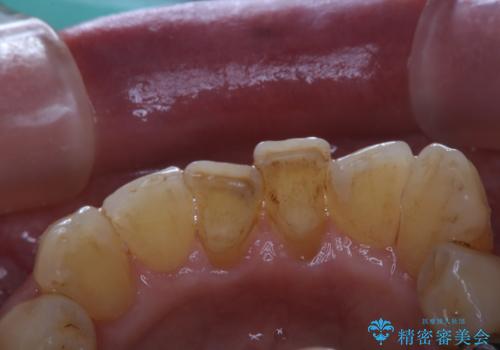

インビザラインで矯正中のコーヒーによる着色をきれいに除去

- インビザライン中に、コーヒーによる着色が気になるとのことでした。PMTC60分コースを行いました。

PMTC(保険外治療)は、毎日の歯磨きで落としきれない汚れや、コーヒ、紅茶・タバコのヤニなどの着色も除去します。目には見えない歯と歯の間・歯肉の境目・インビザライン中はアタッチメント周囲などに残っているプラーク(歯垢)もしっかり取り除きます。PMTCでは専門的な機械や材料を使用して、徹底的に汚れを除去するため、虫歯・歯周病・口臭予防などにつながります。

またPMTCを行うことで、ご自身本来の歯の色になり自然な明るさになります。

口元が自然な明るさになることで、より清潔感のある印象になるため結婚式・行事やイベント前などにもPMTCを行うはおすすめです。